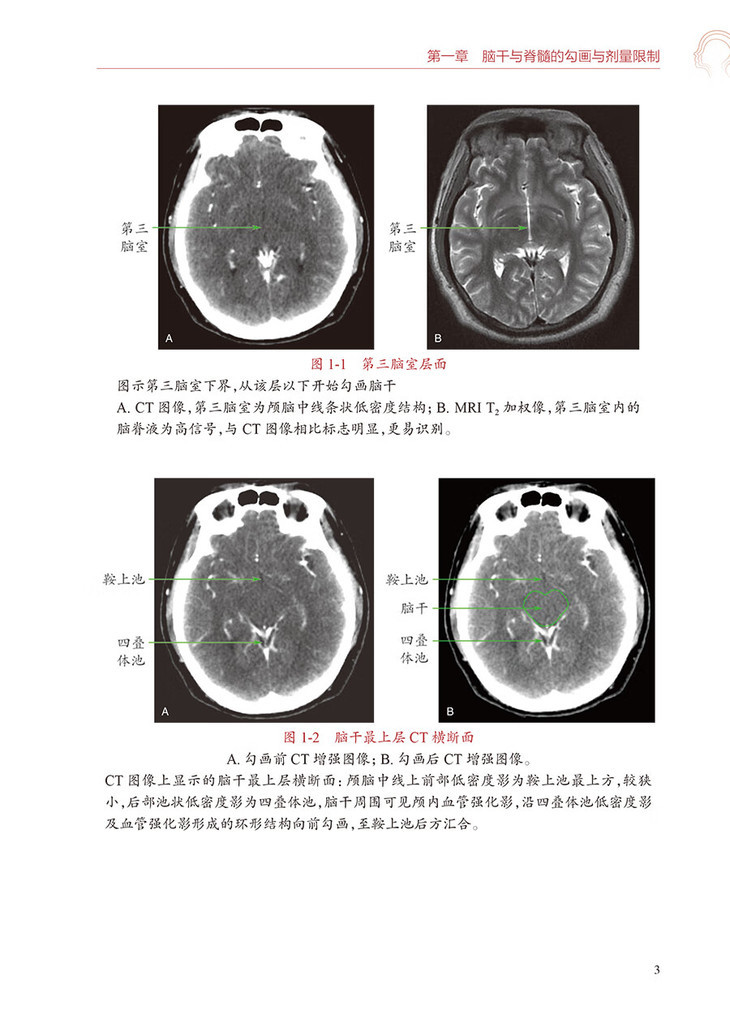

第二节勾画图谱/2